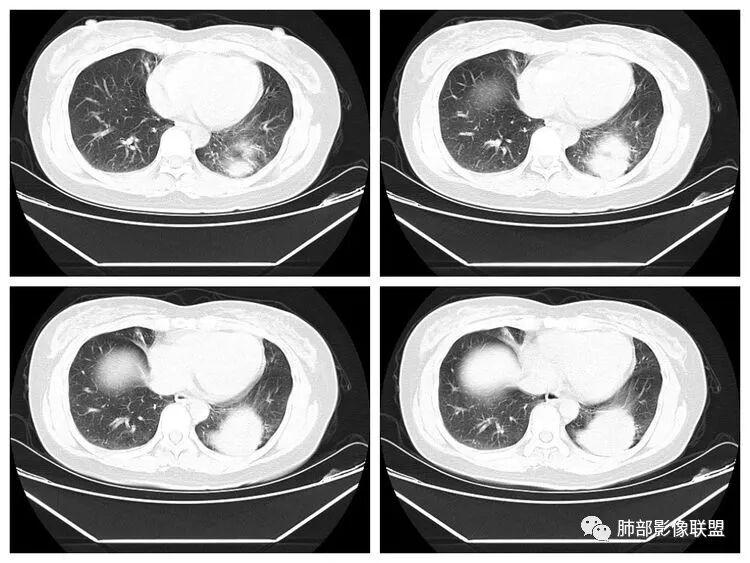

看完第二部分大家再说说看有什么体会?宇宙星空:左侧膈面上片状高密度影

Coke with ice:平片真不容易观察。这里最常见的是什么毛病呢……后肋膈角,呃……疝?形态不太像疝。还有啥疾病谱,盘状肺不张?胸膜来源?

Shelia:尤其体检基本不照侧位片Coke with ice:嗯,很有警示意义的病例。我倾向于定位胸膜来源,SFT?

M-Imaging :错了,这么大,膈肌后方南边:定位?定性?Shelia:肺外。感觉病灶是个扁平状,虽然没有蛇纹血管征,但是延迟强化,怀疑纤维来源,考虑sft

M-Imaging :肿块与胸膜夹角是锐角,有分叶,觉得肺内Lotus:mpr重建再看一下南边:与支气管有关系吗Shelia:没有关系。与胸膜分不清

宇宙星空:没有关系。长轴与胸膜平行吧?

Coke with ice:与肺韧带有关系。与肺韧带的夹角呈钝角,感觉有胸膜尾

宇宙星空:糊墙关系:

南边:边缘这么光滑,无分叶,与胸膜关系密切

D字征

首先良性,倾向于SFT,不除外PSP

小微:肺外肿瘤